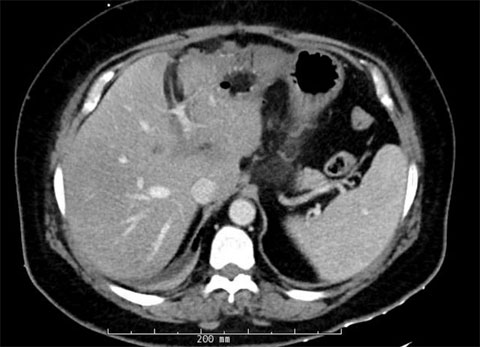

The patient responded well to chemotherapy; in a six-month period from December 2021 to May 2022, there was a significant interval decrease in the size of multiple hepatic metastatic lesions. The patient had approximately 22 peripherally enhancing liver metastases.

Pre-treatment MRIs